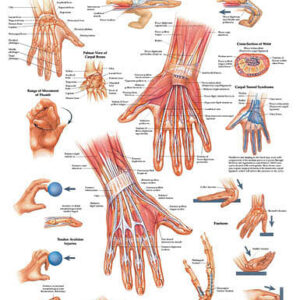

- Orthopedic Care

- Orthopedic Care